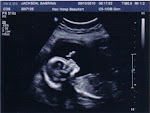

When we got there, the girl checking us in told me she didnt think they would let me bring them in but she asked and they said it was fine. The few wives that were there waiting to see their husbands knew what I was trying to do. The place isn't big and they heard me talking about it. Of course, they're all curious and wanting to know now too. LOL!!!! We get in the room and I see TJ, give him a hug and a kiss and tell him Happy Birthday and thats about as far as I get. I have to know. So he looks at the pictures that I have and then we pull out the sealed pictures. We look together and I can't help but get SUPER excited and say, "I told you it was a girl," The whole room busts out laughing, even the guards. Poor TJ just put his head in hands. He's speechless and completely shocked. He really thought there was no way it could be a girl. To be honest, I think he's slightly disappointed even though he won't say it. I told him it was OK to be. It happens and I know he'll be fine with it but he still won't admit it. Of course, I think he's scared to have a girl too, but I know he'll do fine.